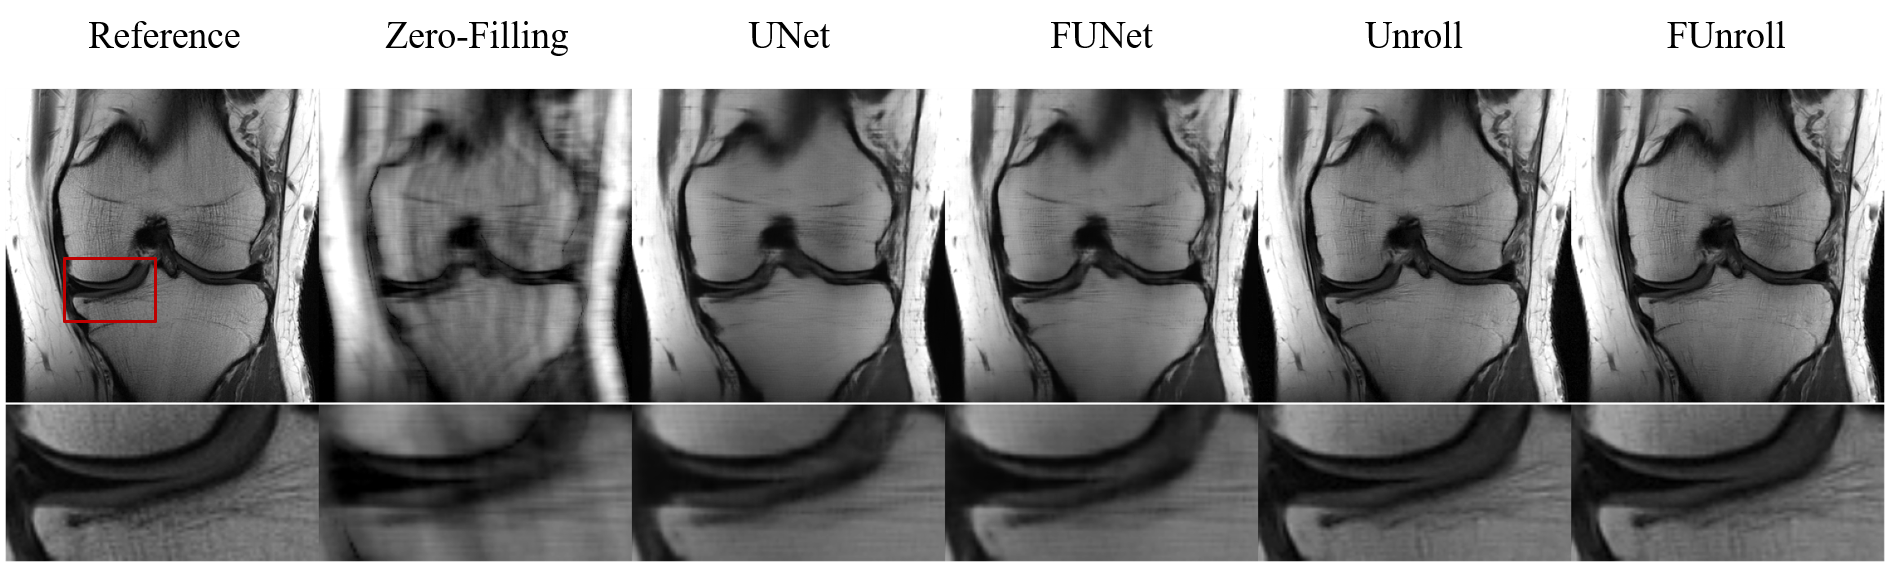

All the quantitative results are shown in Table 1. FCB could improve model’s performance in single-coil and multi-coil data at 4× and 8× acceleration. In particular, the proposed method can get the better numerical results for unroll model in high reduction factor, which indicates that the proposed method have strong robustness. Figure 2 shows the reconstructed result of multi-coil data at 4× acceleration from baseline model and its variant with FCB. The proposed method has the best reconstruction of the meniscus in the unroll model as shown in the red box. Figure 3 shows results at 8× acceleration. It can be seen that the proposed method still has better image reconstruction results under high reduction factor. UNet has a heavy smoothing effect on images and FCB helps to recovery details. For Unroll model, FCB version behaves well in the texture and detail of skeleton and cartilage. Besides, we visualize the trained production kernel in frequency domain as shown in Figure 4. Because Fourier transform is orthogonal, the rank of kernel is constant between frequency domain and spatial domain. The trained kernels have the rank larger than the fixed value of CNN model, which corresponds to large spatial filter with large receptive field.

Figure 2.Example reconstructions of multi coil data at 4 × acceleration. The content in red box is zoomed in to show details. The unroll model with FCB has the best reconstruction of the meniscus.